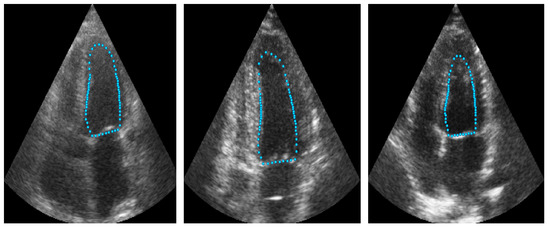

4.4. Improved ASM with ShapeNet Initialization

Following the algorithm depicted in Figure 8, the contour predicted by ShapeNet was used to automatically initialize the ASM described in Section 3.3. The result of combining these two methods can be observed in Figure 13 and Figure 14 for systole and diastole, respectively. In Table 3 is shown the Dice coefficient and Hausdorff distance for each of the test sets (CAMUS and EchoNet), with overall values of 0.83 for Dice and 7.36 pixels for Hausdorff distance.

Figure 13.

ShapeNet + improved ASM systole segmentation examples for CAMUS (top) and EchoNet (bottom) images.

Figure 14.

ShapeNet + improved ASM diastole segmentation examples for CAMUS (top) and EchoNet (bottom) images.

Our proposed ASM was used to improve the accuracy of the final segmentation of the LV. This ASM proved to be more accurate than the original ASM reported in [30]. In our capture range tests (see Figure 10), the improved ASM produced smaller mean values for the Hausdorff distance. Additionally, in some cases, when the initialization pose values were far from the ventricle contour, the original ASM failed to converge, causing run-time errors when the LV model grew outside the image. Table 1 shows that, for the improved ASM, the number of run-time errors was exceptionally low compared to the ASM reported in [30]. The improvements in accuracy and robustness of our ASM are most likely due to the use of all the gray level profiles concatenated in a single vector, as well as the objective function, which together provide the means to evaluate the image fitting of a whole ventricle contour, instead of the local adjustment point-by-point performed in the original ASM, and this was reflected in the final segmentation of the LV for the EchoNet dataset, as seen in Table 5 and in Figure 13 and Figure 14.